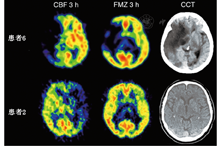

3.缺血半暗带的无创性显像。15O PET测量脑血流量与OEF需要动脉采血,而神经元完整性的测量无需动脉采血,可监测脑血管疾病发生不可逆损伤的不同时间点的生物标志物。氨基丁酸受体在大脑皮质表达丰富,能与中枢型苯二氮受体配体11C-氟马西尼结合。这些受体对缺血性损伤较敏感,可以识别早期的神经元损伤。11C-氟马西尼(图3)可以准确鉴定缺血性脑卒中早期的病理生理改变:在脑卒中发生后的第1个小时,55%的梗死区域有11C-氟马西尼摄取;21%的梗死区域血流量低于14 ml·100 g-1·min-1,而11C-氟马西尼的摄取高于临界值,表明该区域为缺血半暗带[44]。皮质的11C-氟马西尼摄取减低,可能是在缺血半暗带的周围或再灌注组织的缺血半暗区内有选择性的神经元缺失[52]。与SPECT显像剂对比,123I-碘西尼可在缺血性脑卒中的亚急性或慢性阶段对组织的不可逆损伤进行监测[53]。123I-碘西尼在缺血脑组织中的摄取与PET监测的CMRO2和OEF相关[54],且其在脑低灌注区的摄取能够滞留。123I-碘西尼SPECT显像中的梗死区域与MRI中的神经元缺失区域匹配[55],可用以判别哪些脑卒中患者梗死后从神经损伤中恢复会有较好或中度的预后。

有10%的大脑中动脉区域脑卒中患者会发展为恶性脑梗死。侵入治疗特别是去骨瓣减压术,可以降低这些患者的死亡率和发病率[70]。干预治疗是否有效以及干预治疗的最佳时间选择仍存争议,故需要更好地评估脑缺血不可逆损伤的方法。在34例患者中,超过50%的患者在大脑中动脉缺血区域的早期CT扫描上有变化,11C-氟马西尼PET显像可评估CBF和不可逆的神经组织损伤(图3)。随后,微透析探针和测量颅内压及组织氧分压的探针可分别进入同侧额叶[71]。在脑卒中发生后的24 h内,恶性病变患者(水肿形成与中线移位)与良性病变患者的病理改变相比,PET显像可见1个大的梗死灶核心(均值为144.5与62.2 cm3)以及体积较大的神经组织不可逆损伤病灶(均值为157.9与47.0 cm3)(图3)。在缺血病灶内CBF平均值明显降低,恶性病变的缺血半暗带体积明显小于良性病变组。在患者缺血病灶的恶性进程中,在症状发作后的22~72 h(平均为52 h)内脑灌注压下降至50~60 mmHg,随后,组织氧分压下降,谷氨酸增加,发生继发性缺血。谷氨酸、天冬氨酸、γ-氨基丁酸、甘油、乳酸-丙酮酸比值、次黄嘌呤、颅内压、脑灌注压、组织氧分压等监测值的变化达到最大水平。PET与实验研究相同,能够为恶性大脑中动脉梗死的颅内减压术提供早期干预治疗的时间窗;相反,侵入性监测并没有为恶性病灶的早期干预治疗提供一个足够早的时间窗。